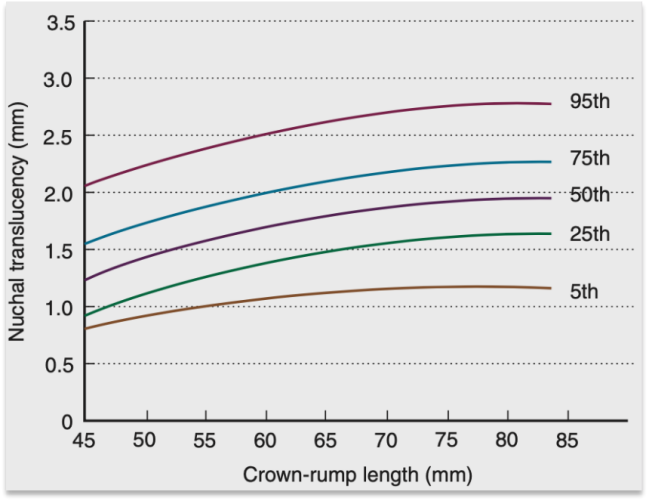

2. NT值正常范围及增厚判断

正常妊娠11周至13周6天,颈项透明层厚度会随孕周略微上升,不同孕周的NT判断标准不同,不可一概而论:

l 11 周:第 95 百分位约 2.0mm

l 13 周 + 6 天:第 95 百分位约 2.7mm

l 部分医院:采用≤2.5mm或≤3.0mm的判断标准

l 目前公认:当NT值大于第99百分位(即3.5mm)时,可明确判定为NT增厚。

总之,数值越高,胎儿异常风险相对越高。

图片来自Creasy and Resnik’s Maternal-Fetal Medicine PRINCIPLES AND PRACTICE 7TH Edition